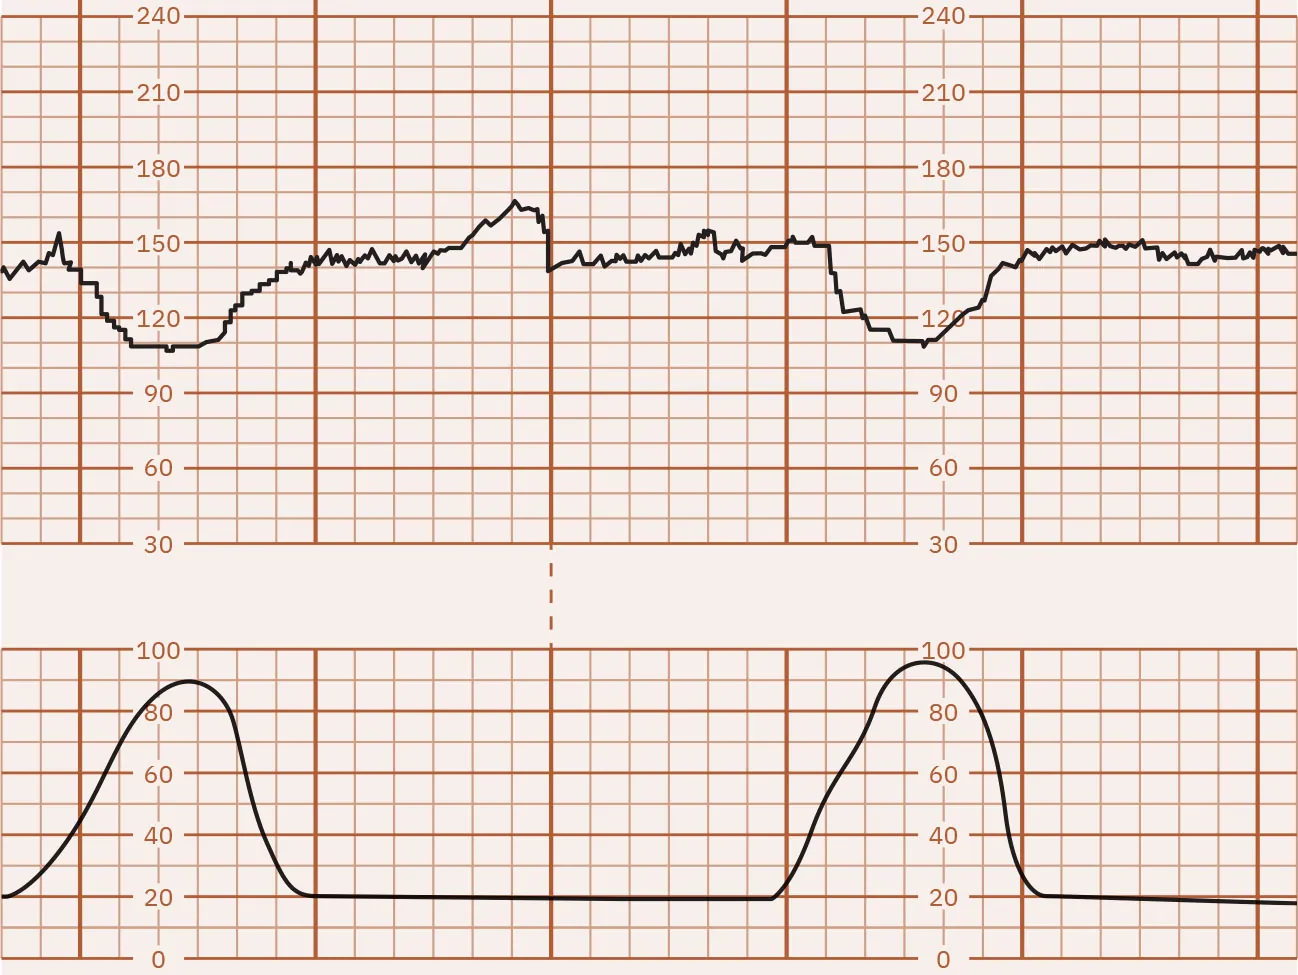

Early Decelerations

Gradual FHR declines that then return to baseline, mirroring the uterine contraction, are called early decelerations. Fetal head compression activates the vagal nerve, causing a deceleration in the FHR. The degree of deceleration is proportional to the strength of the uterine contraction. Decelerations are commonly seen during active labor as the fetal head descends into the pelvis. Early decelerations are considered normal. Figure 16.11 illustrates early FHR decelerations.

Fetal heart rate reading indicating early decelerations.

Figure 16.11 Monitor Tracing Showing Early Decelerations of the FHR These FHR decelerations are early because they mirror the uterine contraction. (attribution: Copyright Rice University, OpenStax, under CC BY 4.0 license)